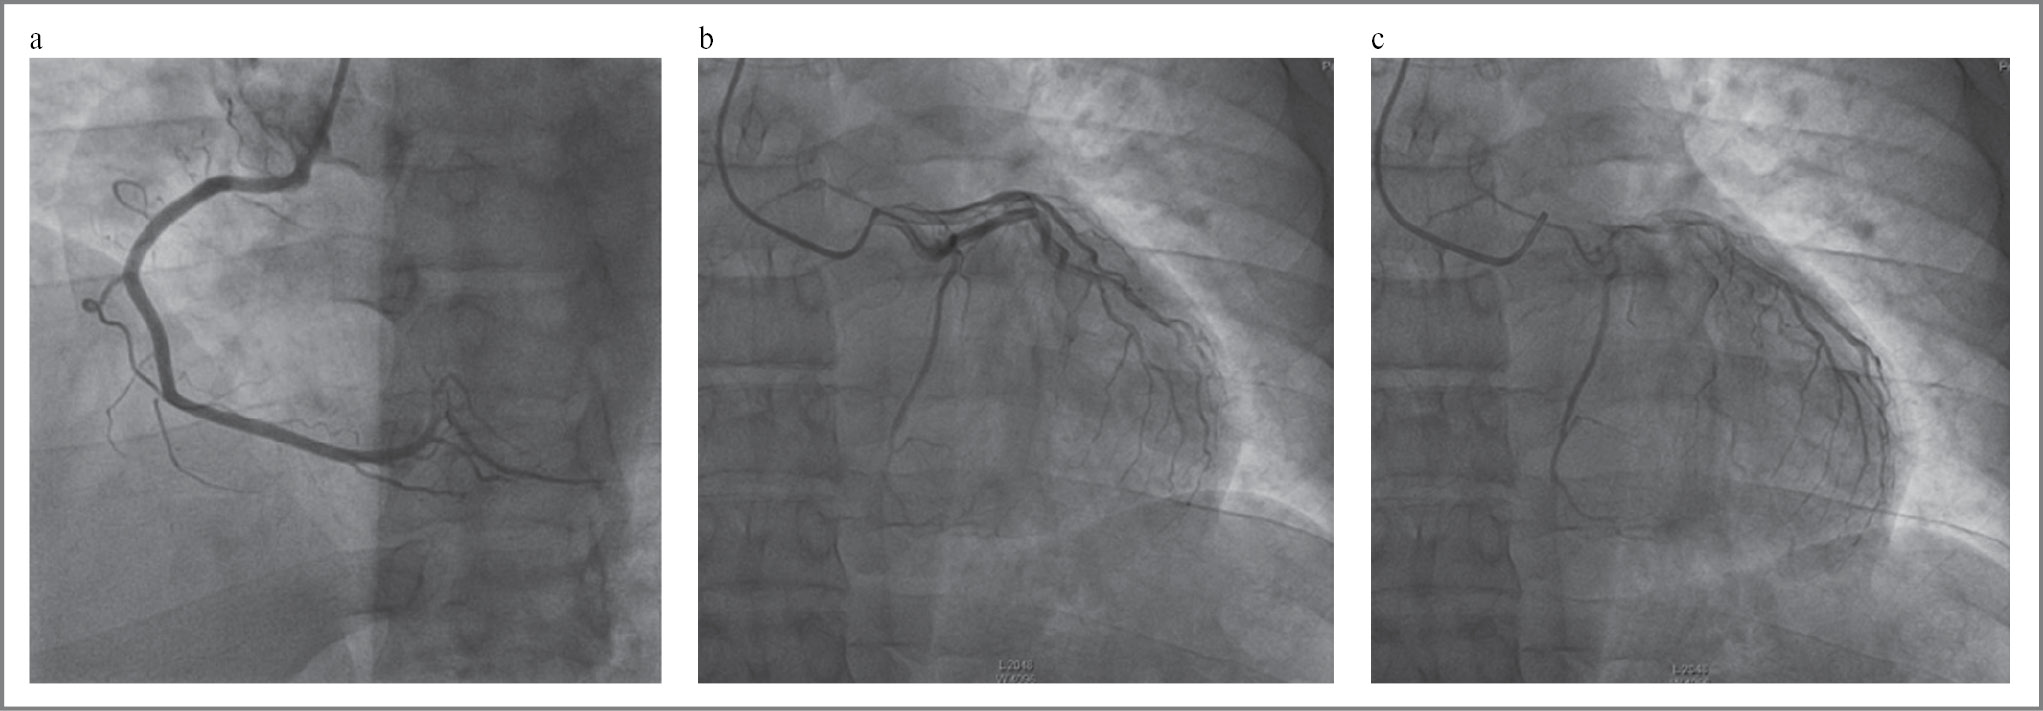

Госпитализирован в больницу скорой медицинской помощи. По данным коронарографии от 05.03.2023: (рис. 2) стенозов коронарных артерий не выявлено. Выраженный вазоспазм левой коронарной артерии (ЛКА).

Рис. 2. Коронарография: a – правая коронарная артерия без значимых стенозов; b, c – вазоспазм ЛКА.

Fig. 2. Coronary angiography: a – absence of stenoses in the right coronary artery; b, c – left coronary artery vasospasm pattern.